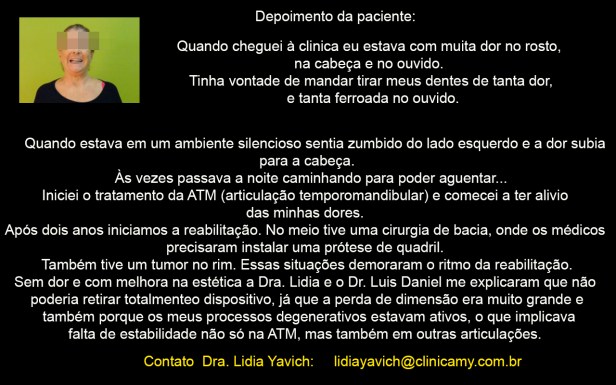

Depoimento da paciente:

Quando cheguei à clinica eu estava com muita dor no rosto, na cabeça e no ouvido. Tinha vontade de mandar tirar meus dentes de tanta dor, e tanta ferroada no ouvido.

Quando estava em um ambiente silencioso sentia zumbido do lado esquerdo e a dor subia para a cabeça. Às vezes passava a noite caminhando para poder aguentar…

Iniciei o tratamento da ATM (articulação temporomandibular) e comecei a ter alivio das minhas dores.

Após dois anos iniciamos a reabilitação. No meio tive uma cirurgia de bacia, onde os médicos precisaram instalar uma prótese de quadril.

Também tive um tumor no rim e os médicos precisaram removê-lo.

Essas situações demoraram o ritmo da reabilitação.

Sem dor e com melhora na estética a Dra. Lidia e o Dr. Luis Daniel me explicaram que não poderia retirar totalmente o dispositivo, já que a perda de dimensão era muito grande e também porque os meus processos degenerativos estavam ativos, o que implicava falta de estabilidade não só na ATM, mas também em outras articulações.

Fiquei com um dispositivo intraoral pequeno que vai ser trocado em pouco tempo por um dispositivo intra-oral estético.

Minha qualidade vida melhorou 100 por cento, eu consigo dormir muito bem, e até o zumbido não sinto mais, nem as ferroadas.

ESTÉTICAMENTE MELHOROU A MINHA AUTOESTIMA, mesmo que isso não TENHA SIDO o motivo da procura. O motivo era aliviar as minhas dores, agora SEM DOR, TAMBÉM A ESTÉTICA É IMPORTANTE.

Grande abraço e o agradecimento aos meus Drs, Lidia e Dr. Luis Daniel, pela qualidade de vida.